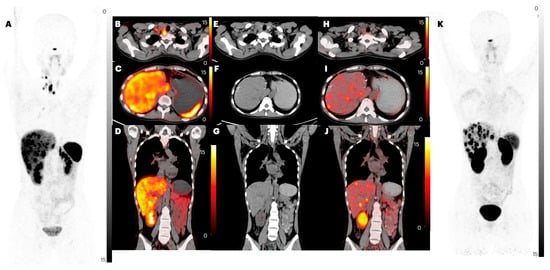

2.2.3. Lung Metastases

2.2.5. Bone Metastases

| Parameters | Imaging Method | Primary | Lymph Node Metastasis | Lung Metastasis | Liver Metastasis | Bone Metastasis |

| Patient-based analysis | ||||||

| CT | 33 | 31 | 8 | 31 | 6 | |

| [68Ga]Ga-DOTANOC | 28 (84.8%) | 23 (74.1%) | 0 (0%) | 26 (83.9%) | 6 (100%) | |

| [68Ga]Ga-DATA5m-LM4 | 28 (84.8%) | 23 (74.1%) | 0 (0%) | 28 (90.3%) | 6 (100%) | |

| p-value | 1.000 | 1.000 | - | 0.449 | 1.000 | |

| CT | 47 | 107 | 12 | 283 | 41 | |

| [68Ga]Ga-DOTANOC | 40 (85.1%) | 82 (76.6%) | 0 (0%) | 253 (89.4%) | 34 (82.9%) | |

| [68Ga]Ga-DATA5m-LM4 | 42 (89.4%) | 83 (77.6%) | 0 (0%) | 292 (value greater than CT) = 100% | 45 (value greater than CT) = 100% | |

| p-value | 0.544 | 0.862 | - | <0.0001 | 0.005 | |